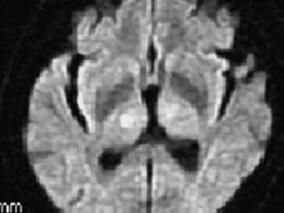

1小时条评论基底动脉尖综合征(top of the basilar artery syndrome,TOBS)为基底动脉首端区域血液循环障碍所致的以丘脑、枕叶、颞叶内侧面、中脑、脑桥、小脑梗死为主要表现的一组临床综合征。 自1980年Caplan提出TOBS后,已日渐引起重视,国内也已经有较大病例数的报道,但...

1小时条评论基底动脉尖综合征并不少见,然而,先天椎动脉变异形成类基底动脉尖样影像学表现的个体却没有相同的。 临床资料 患者男性,50岁,2008年8月8日9:30入院,眩晕、呕吐,左侧肢体无力2小时。患者于入院当日晨起散步后,7:30洗漱中,用力咳嗽清理咽喉时突感天旋地转,...